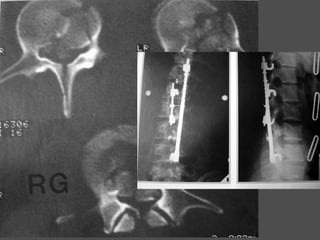

Secondary survey (ATLS)

Spinal injury

Thorough sensory and motor examination

โ€ข Prevent further damage in unstable

fractures

โ€ข Log rolling for full neurological

examination-5 people required

โ€ข Use a long spine board for transportation